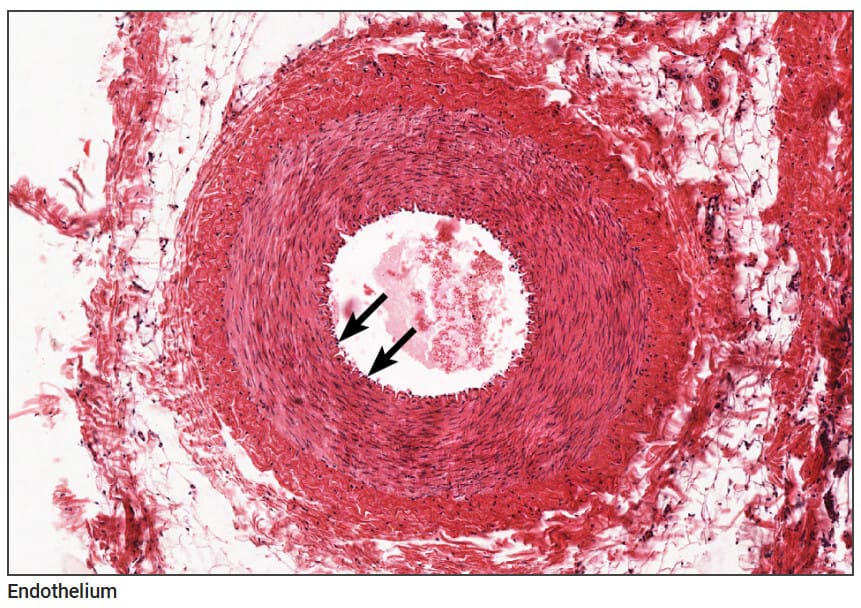

내막 (Tunica Intima)

| 내막 (Tunica Intima) |

| ✅ 단층 편평상피(endothelium)와 그 아래 얇은 결합조직층(subendothelial layer)로 구성되어 있으며, 내막과 중막 사이에는 뚜렷한 내부 탄성판(internal elastic lamina)이 존재합니다. 조직학적으로 물결 모양 또는 굵은 띠로 보이며, 근육 동맥의 특징적 소견입니다. |

중막 (Tunica Media)

| 중막 (Tunica Media) |

| ✅ 주로 원형 배열의 민무늬근(smooth muscle cells)으로 구성되며, 일반적으로 5~40층 정도 존재합니다. |

| 탄성 섬유보다 근육층이 더 두드러지며, 혈관의 수축과 이완을 통해 혈류를 조절합니다. 섬유아세포와 교원질이 일부 포함될 수 있습니다. |

| 외부 탄성판(external elastic lamina)이 중막과 외막 사이에 존재할 수 있습니다. |